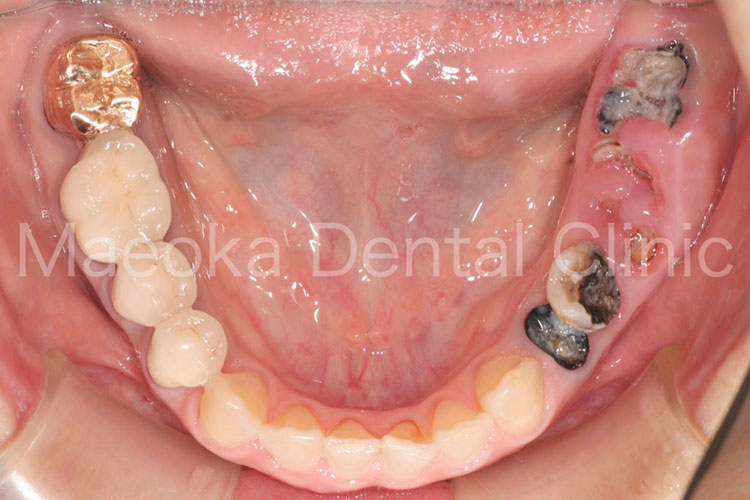

患者さんは58歳の男性の方で、「右下の歯がグラグラして痛いので診て欲しい」という主訴で来院されました。お口の中を拝見すると重度の歯周病を認めました。1日1箱近い本数の喫煙があったこともあり、歯肉は血行不良を起こして黒っぽい印象がありました。

初診時には歯周病の原因と「どうすれば歯周病は治るのか」、「再発を防ぐためには何が必要なのか」を説明し、歯磨きのトレーニングをスタートしました。その後、患者さんのプラークコントロールレベルが向上したタイミングで歯石を取り、基本治療を終えました。その後、義歯を入れるなどの機能回復も検討しましたが、患者さん自身が不都合を感じていなかった点、レントゲン上でも残存歯の負担が増加している所見が見られなかった点を考慮し、経過観察としています。

主訴の右下7は失うことになってしまいましたが、その他の歯は現在のところ1本も失うことなく経過しています。現在も喫煙はありますが、歯肉は引き締まり、健康な組織を取り戻しています。今後はメインテナンスを通してプラークコントロールレベルの維持に患者さんと取り組んでいきます。

初診時の右下大臼歯部